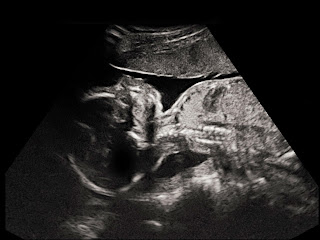

LISTEN NOW! There have been numerous bills regarding abortion that have gone before our nation’s leaders. This one being presented to the House of Representatives, The Pain Capable Unborn-Child Protection Act, addresses any abortion after the 20-week mark as criminal in the awareness that these babies can feel the excruciating pain that takes place during such an operation of an abortion. CBN is reporting, that based on the bill, “doctors who violate the law could be subject to fines and up to five years in prison.” This would be a major victory for the Pro-life community.